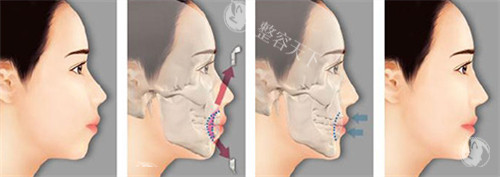

真人实例:下颌角截骨蜕变记

病例背景28岁女性因下颌角外翻导致"国字脸",伴有明显不对称,经何医生采用"长曲线截骨术"矫正。

手术过程术中同步进行咬肌修薄和颊脂垫调整,手术时长2.5小时,出血量仅80ml。

修养结果术后3个月面部线条流畅自然,咬合功能完全正常,侧面轮廓提升30°。